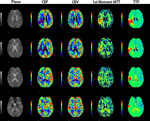

■ 脳血流解析ソフト

頭部領域においてダイナミックCTおよびMRのデータを画像処理し、脳の血流状態を定量的および視覚的に評価します。Deconvolutionを用いた脳血流量(CBF)/脳血液量(CBV)/平均通過時間(MTT)、TDCから算出した造影剤到達ピーク時(TTP)/平均通過時間(MTT)を計測してマッピングします。さらにMRでは1st Moment法によるMTTの算出が可能です。

「Auto Registration」「Auto Window」「Auto AIF」の3つのAuto機能で高度な解析を実現します。

脳血流解析ソフト